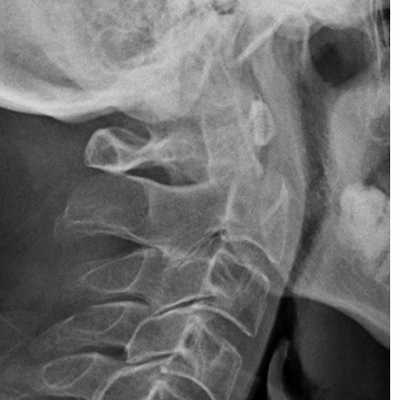

Рентгенограмма. Подвывих в шейном отделе позвоночника. Цветовая обработка изображения.

Половина всех случаев переломов позвоночника приходится на шейный отдел. Многие травмы шейного отдела позвоночника угрожают жизни пациента для жизни пациента. Поэтому они требуют неотложных мероприятий.

Обследование начинается со стандартной рентгенографии в 3 проекциях – боковой, передне-задней (прямой) и через рот.